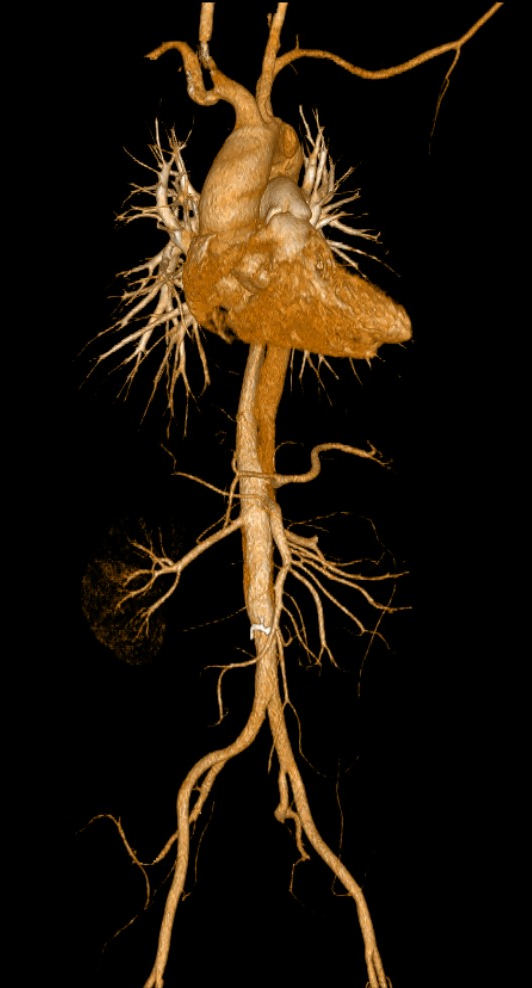

全身各部位血管造影:Incisive CT可以轻松实现大范围CT血管造影(CTA),准确了解血管及相关脏器的形态结构,评估血管及脏器功能,准确判断出血,栓塞、血管瘤、血管畸形、狭窄及肿瘤供血情况,为临床治疗提供极大帮助。

▲ 胸腹部CTA-主动脉夹层一目了然

飞利浦Incisive AI CT还具备3D重建成像技术,能够将复杂的解剖结构以三维的形式呈现出来,为医生提供更为直观的视觉辅助,从而帮助医生更好地理解和解释病变情况,提升诊断准确性。